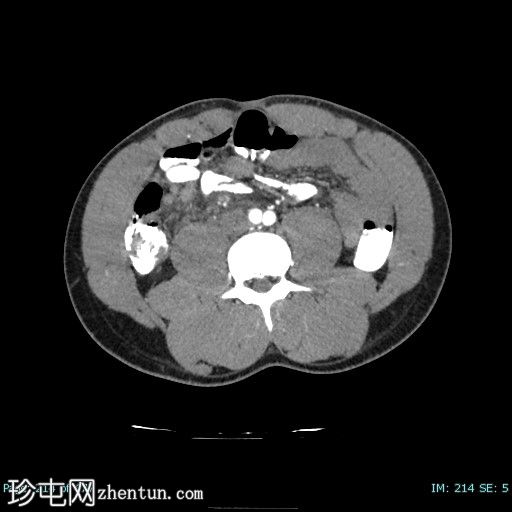

3.png

轴位增强扫描

门静脉期

阑尾壁增厚并强化。

阑尾与一个厚壁强化脓肿相连,脓肿大小约3.2 x 4.3 cm(横径 x 纵径),内含气体。

周围肠系膜淋巴结肿大,脂肪浸润,并可见积液。

盲肠极炎症性增厚。

影像学特征提示复杂性阑尾炎伴穿孔及包裹性阑尾脓肿。

此处给予口服造影剂是医院常规操作的一部分。然而,仅使用静脉注射造影剂也能准确诊断阑尾炎,这样可以避免不必要的诊断和手术治疗延误。目前典型的操作流程是进行单次门静脉期扫描(注射后 60-70 秒),造影剂剂量为 1.5 mg/kg,注射速度为 3-4 ml/s。